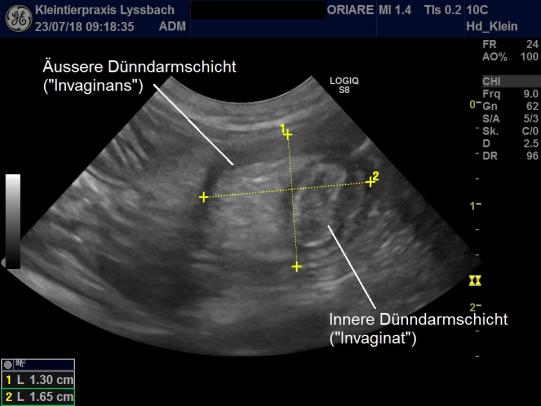

Im Ultraschall findet sich eine abnormale Struktur: Der Dünndarm scheint sich auf einem kurzen Abschnitt zu erweitern und von einer weiteren Struktur ausgefüllt zu sein, welche sonografisch ebenfalls als Darm identifiziert werden kann. Offensichtlich handelt es sich bei dieser "Bull's Eye"-Struktur um eine sogenannte Invagination: Wie ein Strumpf hat sich der Dünndarm an dieser Stelle in sich selbst hinein eingestülpt, blockiert nun das Darmrohr und bewirkt dadurch einen Darmverschluss.